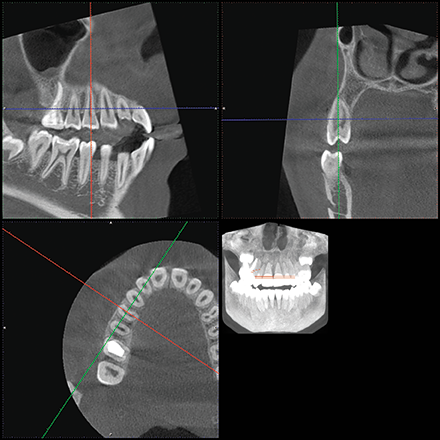

The location of the roots of the maxillary right dentition closely proximate the buccal and palatal cortical plates of the alveolar processes, which were thin particularly at the canine and first premolar with thicker cortex regions lateral to the second premolar and first molar (Figs. 4-7).

Fig. 5 Fig. 6